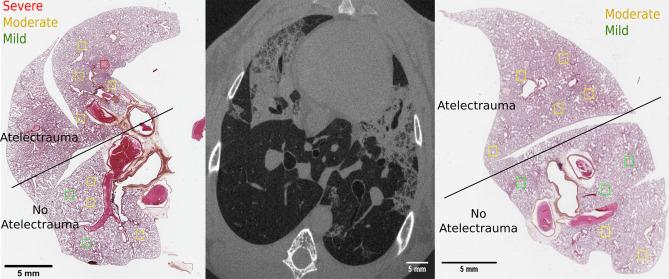

Mechanical ventilation can damage the lungs, a condition called Ventilator-Induced Lung Injury (VILI). However, the mechanisms leading to VILI at the microscopic scale remain poorly understood. Here we investigated the within-tidal dynamics of cyclic recruitment/derecruitment (R/D) using synchrotron radiation phase-contrast imaging (PCI), and the relation between R/D and cell infiltration, in a model of Acute Respiratory Distress Syndrome in 6 anaesthetized and mechanically ventilated New-Zealand White rabbits. Dynamic PCI was performed at 22.6 µm voxel size, under protective mechanical ventilation [tidal volume: 6 ml/kg; positive end-expiratory pressure (PEEP): 5 cmHO]. Videos and quantitative maps of within-tidal R/D showed that injury propagated outwards from non-aerated regions towards adjacent regions where cyclic R/D was present. R/D of peripheral airspaces was both pressure and time-dependent, occurring throughout the respiratory cycle with significant scatter of opening/closing pressures. There was a significant association between R/D and regional lung cellular infiltration (p = 0.04) suggesting that tidal R/D of the lung parenchyma may contribute to regional lung inflammation or capillary-alveolar barrier dysfunction and to the progression of lung injury. PEEP may not fully mitigate this phenomenon even at high levels. Ventilation strategies utilizing the time-dependence of R/D may be helpful in reducing R/D and associated injury.

机械通气可能会损伤肺部,这种情况被称为呼吸机诱导性肺损伤(VILI)。然而,导致 VILI 的微观机制仍知之甚少。在这里,我们使用同步辐射相衬成像(PCI)研究了急性呼吸窘迫综合征模型中周期性复张/复陷(R/D)的潮汐内动力学,以及 R/D 与细胞浸润之间的关系,该模型涉及 6 只麻醉和机械通气的新西兰白兔。在保护性机械通气下[潮气量:6ml/kg;呼气末正压(PEEP):5cmH2O]以 22.6μm 体素大小进行动态 PCI。在潮汐内 R/D 的视频和定量图谱中,发现损伤从非充气区域向外传播,向相邻存在周期性 R/D 的区域传播。周边气腔的 R/D 既与压力有关,也与时间有关,在整个呼吸周期内发生,开/闭压力的离散度很大。R/D 与局部肺细胞浸润之间存在显著相关性(p=0.04),这表明肺实质的潮汐性 R/D 可能导致局部肺炎症或毛细血管肺泡屏障功能障碍以及肺损伤的进展。即使在高水平时,PEEP 也可能无法完全减轻这种现象。利用 R/D 的时间依赖性的通气策略可能有助于减少 R/D 及其相关损伤。